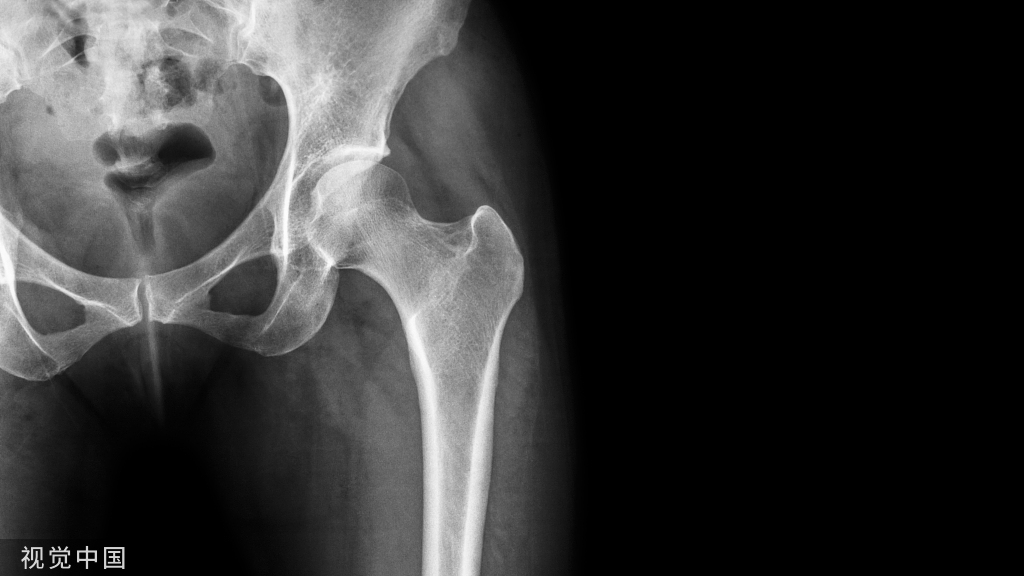

粗隆间骨折的复位可以采用很多方法进行复位。但是有没有更好的方法呢?今天小编告诉你的新方法!不用切开,经皮微创复位,谁用谁知道!

其中重要的原因就是粗隆间骨折的复位,粗隆间骨折复位,我们讲了很多,尤其是在扩髓前,对于移位的患者,可以采用很多方法进行复位。但是有没有更好的方法呢?今天小编告诉你的新方法!不用切开,经皮微创复位,谁用谁知道!